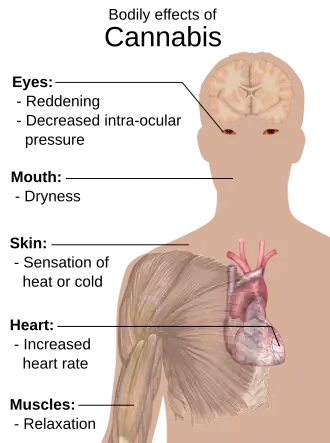

Cannabis has various mental and physical effects, which include euphoria, altered states of mind and sense of time, difficulty concentrating, impaired short-term memory, impaired body movement (balance and fine psychomotor control), relaxation, and an increase in appetite. Onset of effects is felt within minutes when smoked, but may take up to 90 minutes when eaten (as orally consumed drugs must be digested and absorbed). The effects last for two to six hours, depending on the amount used. At high doses, mental effects can include anxiety, delusions (including ideas of reference), hallucinations, panic, paranoia, and psychosis. There is a strong relation between cannabis use and the risk of psychosis, though the direction of causality is debated. Physical effects include increased heart rate, difficulty breathing, nausea, and behavioral problems in children whose mothers used cannabis during pregnancy; short-term side effects may also include dry mouth and red eyes. Long-term adverse effects may include addiction, decreased mental ability in those who started regular use as adolescents,[4] chronic coughing, susceptibility to respiratory infections, and cannabinoid hyperemesis syndrome.

Recreational

Being under the effects of cannabis is usually referred to as being "high".[20] Cannabis consumption has both psychoactive and physiological effects.[21] The "high" experience can vary widely, based (among other things) on the user's prior experience with cannabis, and the type of cannabis consumed.[22]: p647 When smoking cannabis, a euphoriant effect can occur within minutes of smoking.[23]: p104 Aside from a subjective change in perception and mood, the most common short-term physical and neurological effects include increased heart rate, increased appetite, impairment of short-term and working memory, and impairment of psychomotor coordination.[24][25]

Additional desired effects from consuming cannabis include relaxation, a general alteration of conscious perception, increased awareness of sensation, increased libido[26] and distortions in the perception of time and space. In some cases, cannabis can lead to dissociative states such as depersonalization[27][28] and derealization.[29]

Some immediate undesired side effects include a decrease in short-term memory, dry mouth, impaired motor skills, reddening of the eyes,[58] dizziness, feeling tired and vomiting.[14] Some users may experience an episode of acute psychosis, which usually abates after six hours, but in rare instances, heavy users may find the symptoms continuing for many days.[59]